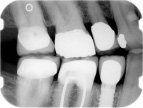

Here is an example of a single dental implant, where there are other missing teeth.

This is an example of multiple dental implants.